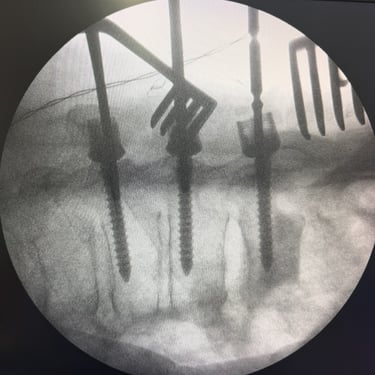

🧠Listesis Lumbar L5–S1 por Fractura Ístmica: Estabilización con FTP y TLIF.

La listesis L5–S1 por fractura ístmica causa inestabilidad y dolor. El tratamiento quirúrgico con FTP y TLIF permite descompresión neural y estabilización vertebral, mejorando la función y calidad de vida.